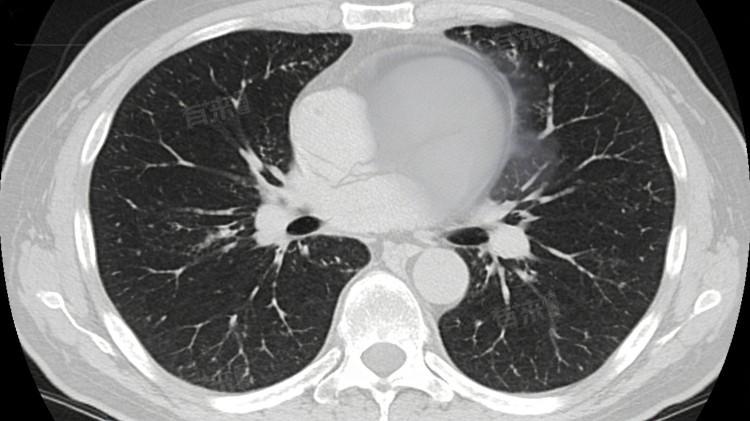

肺部毛玻璃影是肺部CT检查的影像征象,并非独立疾病,多对应肺部局部炎症、渗出、增生等病变,涵盖良性轻症至癌前病变、早期恶性病变,不同病症对应影像特点不同,可通过病变性质区分具体病因。

1、局灶性肺炎:肺部受细菌、病毒等病原体侵袭,引发局部肺泡炎症,肺泡内出现少量炎性渗出物、细胞浸润,肺泡充气程度下降,CT检查呈现淡薄毛玻璃影,边界模糊,伴随咳嗽、咳痰、低热等症状,病变多为暂时性,炎症消退后可逐渐吸收。

2、肺泡出血:肺部毛细血管破裂,少量血液渗入肺泡腔内,未完全填充肺泡,形成毛玻璃样影像改变,多由局部血管损伤、凝血功能轻微异常引发,无明显呼吸道症状,部分可自行吸收,影像表现密度相对均匀。

3、非典型腺瘤样增生:属于肺部肺泡上皮细胞的良性增生性病变,为癌前病变范畴,肺泡上皮细胞异常增生但未突破基底膜,CT显示边界清晰的纯毛玻璃影,直径通常偏小,无明显临床症状,病变进展速度缓慢。

4、真菌性肺炎:肺部感染曲霉菌等真菌,引发局部慢性炎症,肺泡内出现真菌菌丝、炎性渗出及组织增生,形成毛玻璃影,可伴随少量结节,边界欠规整,多见于免疫力偏低人群,抗炎治疗无明显改善。

5、早期肺腺癌:肺部腺上皮细胞发生恶性病变,早期癌细胞沿肺泡壁生长,未形成实性肿块,CT表现为混合性或纯毛玻璃影,边界可清晰或分叶,密度不均,无明显临床症状,属于肺部早期恶性病变范畴。